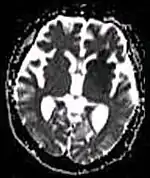

Diffusion weighted (DWI) Conventional DWI Measure of Brownian motion of water molecules.[80] High signal within minutes of cerebral infarction (pictured).[81]

Apparent diffusion coefficient ADC Reduced T2 weighting by taking multiple conventional DWI images with different DWI weighting, and the change corresponds to diffusion.[82] Low signal minutes after cerebral infarction (pictured).[83]